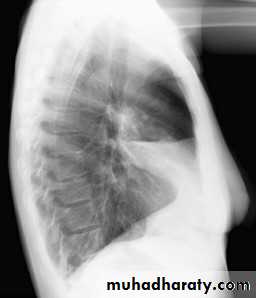

Right middle lobe collapse has distinctive features, and is usually relatively easily identified.

Radiographic features

Chest radiograph

Frontal chest XR showing opasity cause obscuration of the RT cardiac border

Lateral chest XR film the opacity is tongue like shape

versus (triangular in shape) in RT middle lobe consolidation seen in lateral chest XR film